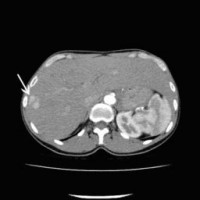

Computertomographische Darstellung eines hepatozellulären Karzinoms (Pfeil)

(Bild 1 von 5)